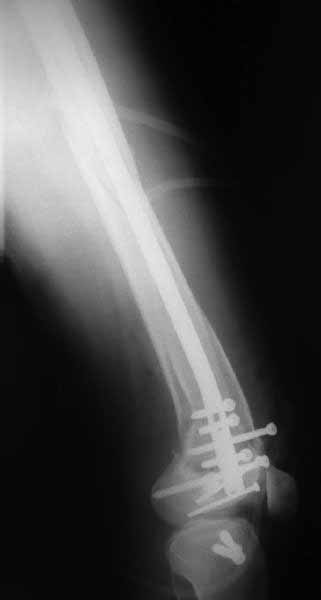

В приложении пример недавней операции, C3, открытая репозиция, фиксация мыщелков спицами и винтами, ретроградный синтез большеберцовым гвоздем 10,5 мм диаметром, винты 5 мм.

Но практика показывает, что классификации существуют не зря, и стоит пользоваться ими, а не ориентироваться на абстрактные "максимально низкие переломы". Подавляющее большинство поступающих к нам больных с дистальными переломами - это C1 и С2. И показанный в прошлом сообщении гвоздик прекрасно справляется. Наверно, сгодятся и многие современные гвозди разных производителей, типа RAFN Synthes. А вот при настоящих C3 одним гвоздем не обойтись, нужны как минимум винты мимо, а то и введение на одном уровне нескольких винтов и/или спиц веером...

На этом большеберцовом стержне центр ближайшего к кондуктору отверстия в 14 мм от конца. И пример был про то, что пластина тут, скорее всего, была бы не худшим выбором.